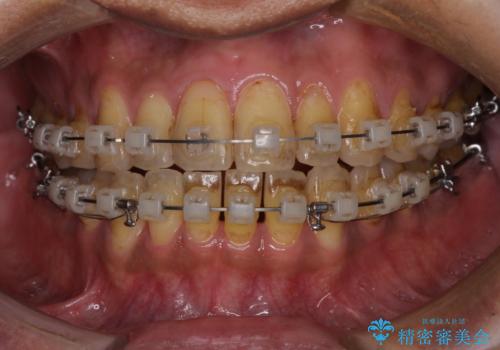

前歯のクロスバイトを改善 ワイヤー装置での非抜歯矯正

- クリアブラケット

- 2年5ヶ月

上下の叢生は速やかに改善できましたが、右側のクロスバイトの改善に1年以上の期間を要しました。